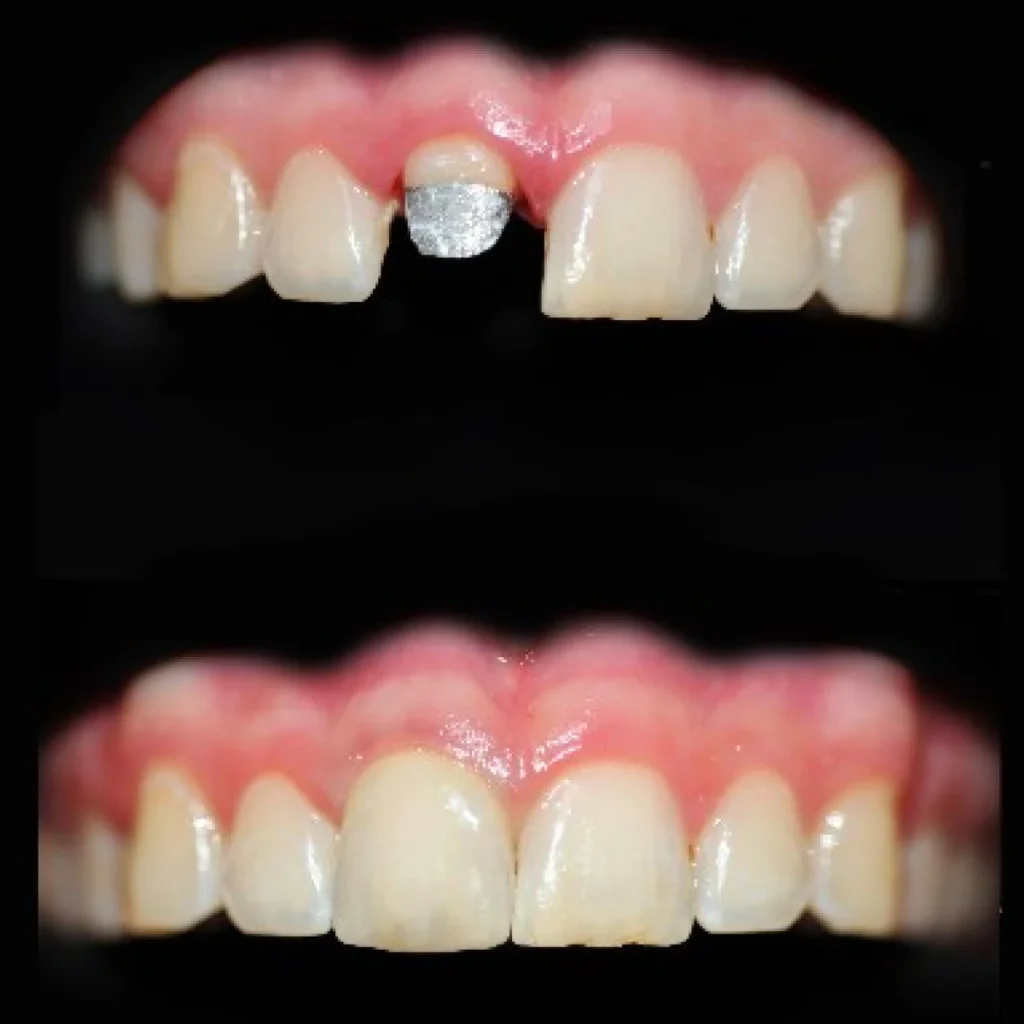

1. Les couronnes dentaires

La couronne est probablement la restauration conjointe la plus répandue. Elle recouvre et protège une dent fragilisée, lui redonne sa forme anatomique et restaure sa fonction masticatoire. Elle est indiquée lorsqu’une dent a été dévitalisée, fracturée, fragilisée par une carie profonde ou simplement trop altérée pour supporter une restauration plus simple.

Différents matériaux peuvent être utilisés dans la fabrication des couronnes :

- Céramique : elle offre un rendu esthétique naturel et se rapproche au plus près de la dent d’origine.

- Zircone : elle combine solidité, fiabilité et esthétique, et convient parfaitement aux zones visibles.

- Métallo-céramique : composée d’une armature métallique recouverte de céramique, elle représente un excellent compromis entre résistance et esthétique.

- Alliages précieux (exemple : or) : particulièrement durables, ils sont utilisés dans certaines situations spécifiques.

Le choix du matériau dépend à la fois du contexte clinique, des attentes du praticien et des souhaits du patient.